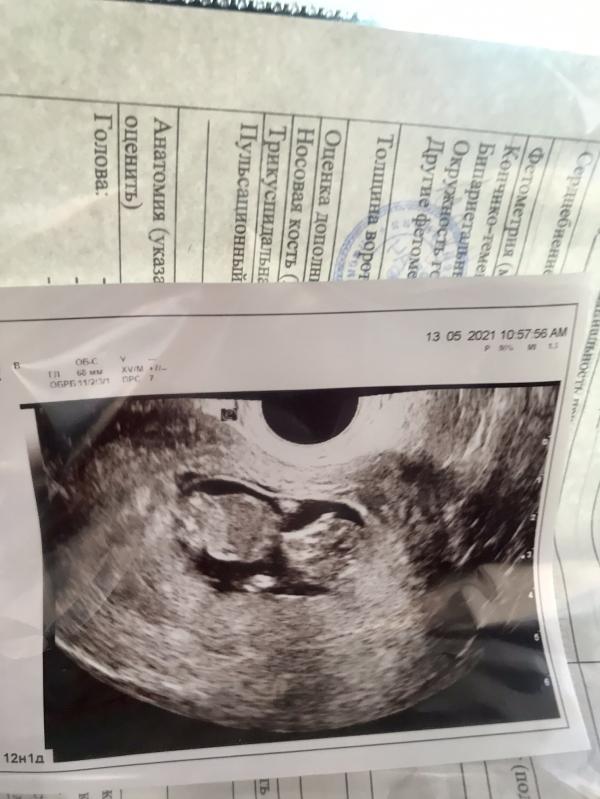

post image

Как быстро ребёнок растёт 😍